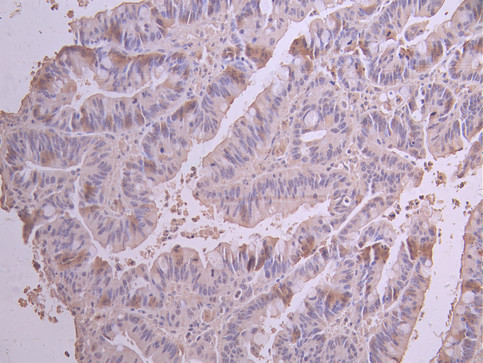

IHC image of CSB-RA848820MA1HU diluted at 1:50 and staining in paraffin-embedded human colorectal cancer performed on a Leica BondTM system. After dewaxing and hydration, antigen retrieval was mediated by high pressure in a citrate buffer (pH 6.0). Section was blocked with 10% normal goat serum 30min at RT. Then primary antibody (1% BSA) was incubated at 4°C overnight. The primary is detected by a Anti-Human lgG, Fcy Fragment Specific labeled by HRP and visualized using 0.05% DAB.